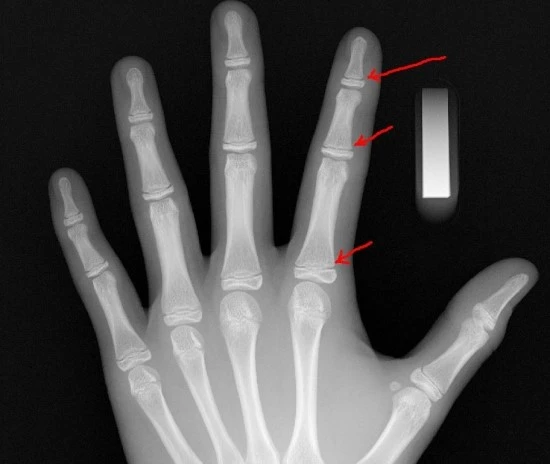

이는 아쉽게도 잘 못된 정보이고, 성장판의 내용은 방사선 검사만을 통해서 확인이 가능하다.

성장을 논하는 성장판은 주로 손목과 어깨를 기준으로 하며,

아래 사진에 있는 왼쪽 손목의 열려있는 골단(open epiphysis)이 시간이 지나면서 오른쪽 손목의 골단처럼 척골과 합쳐진것(closed epiphysis) 을 볼 수 있다.